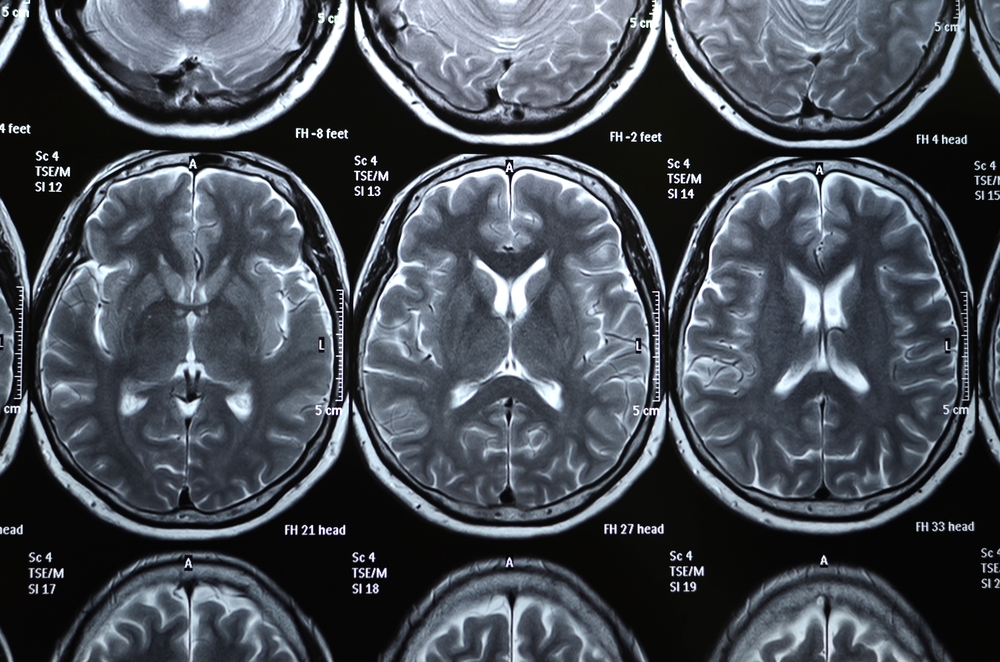

Brains age, just like the rest of the body, even for those don't get neurological disease, according to an Institute of Medicine report released on April 14.